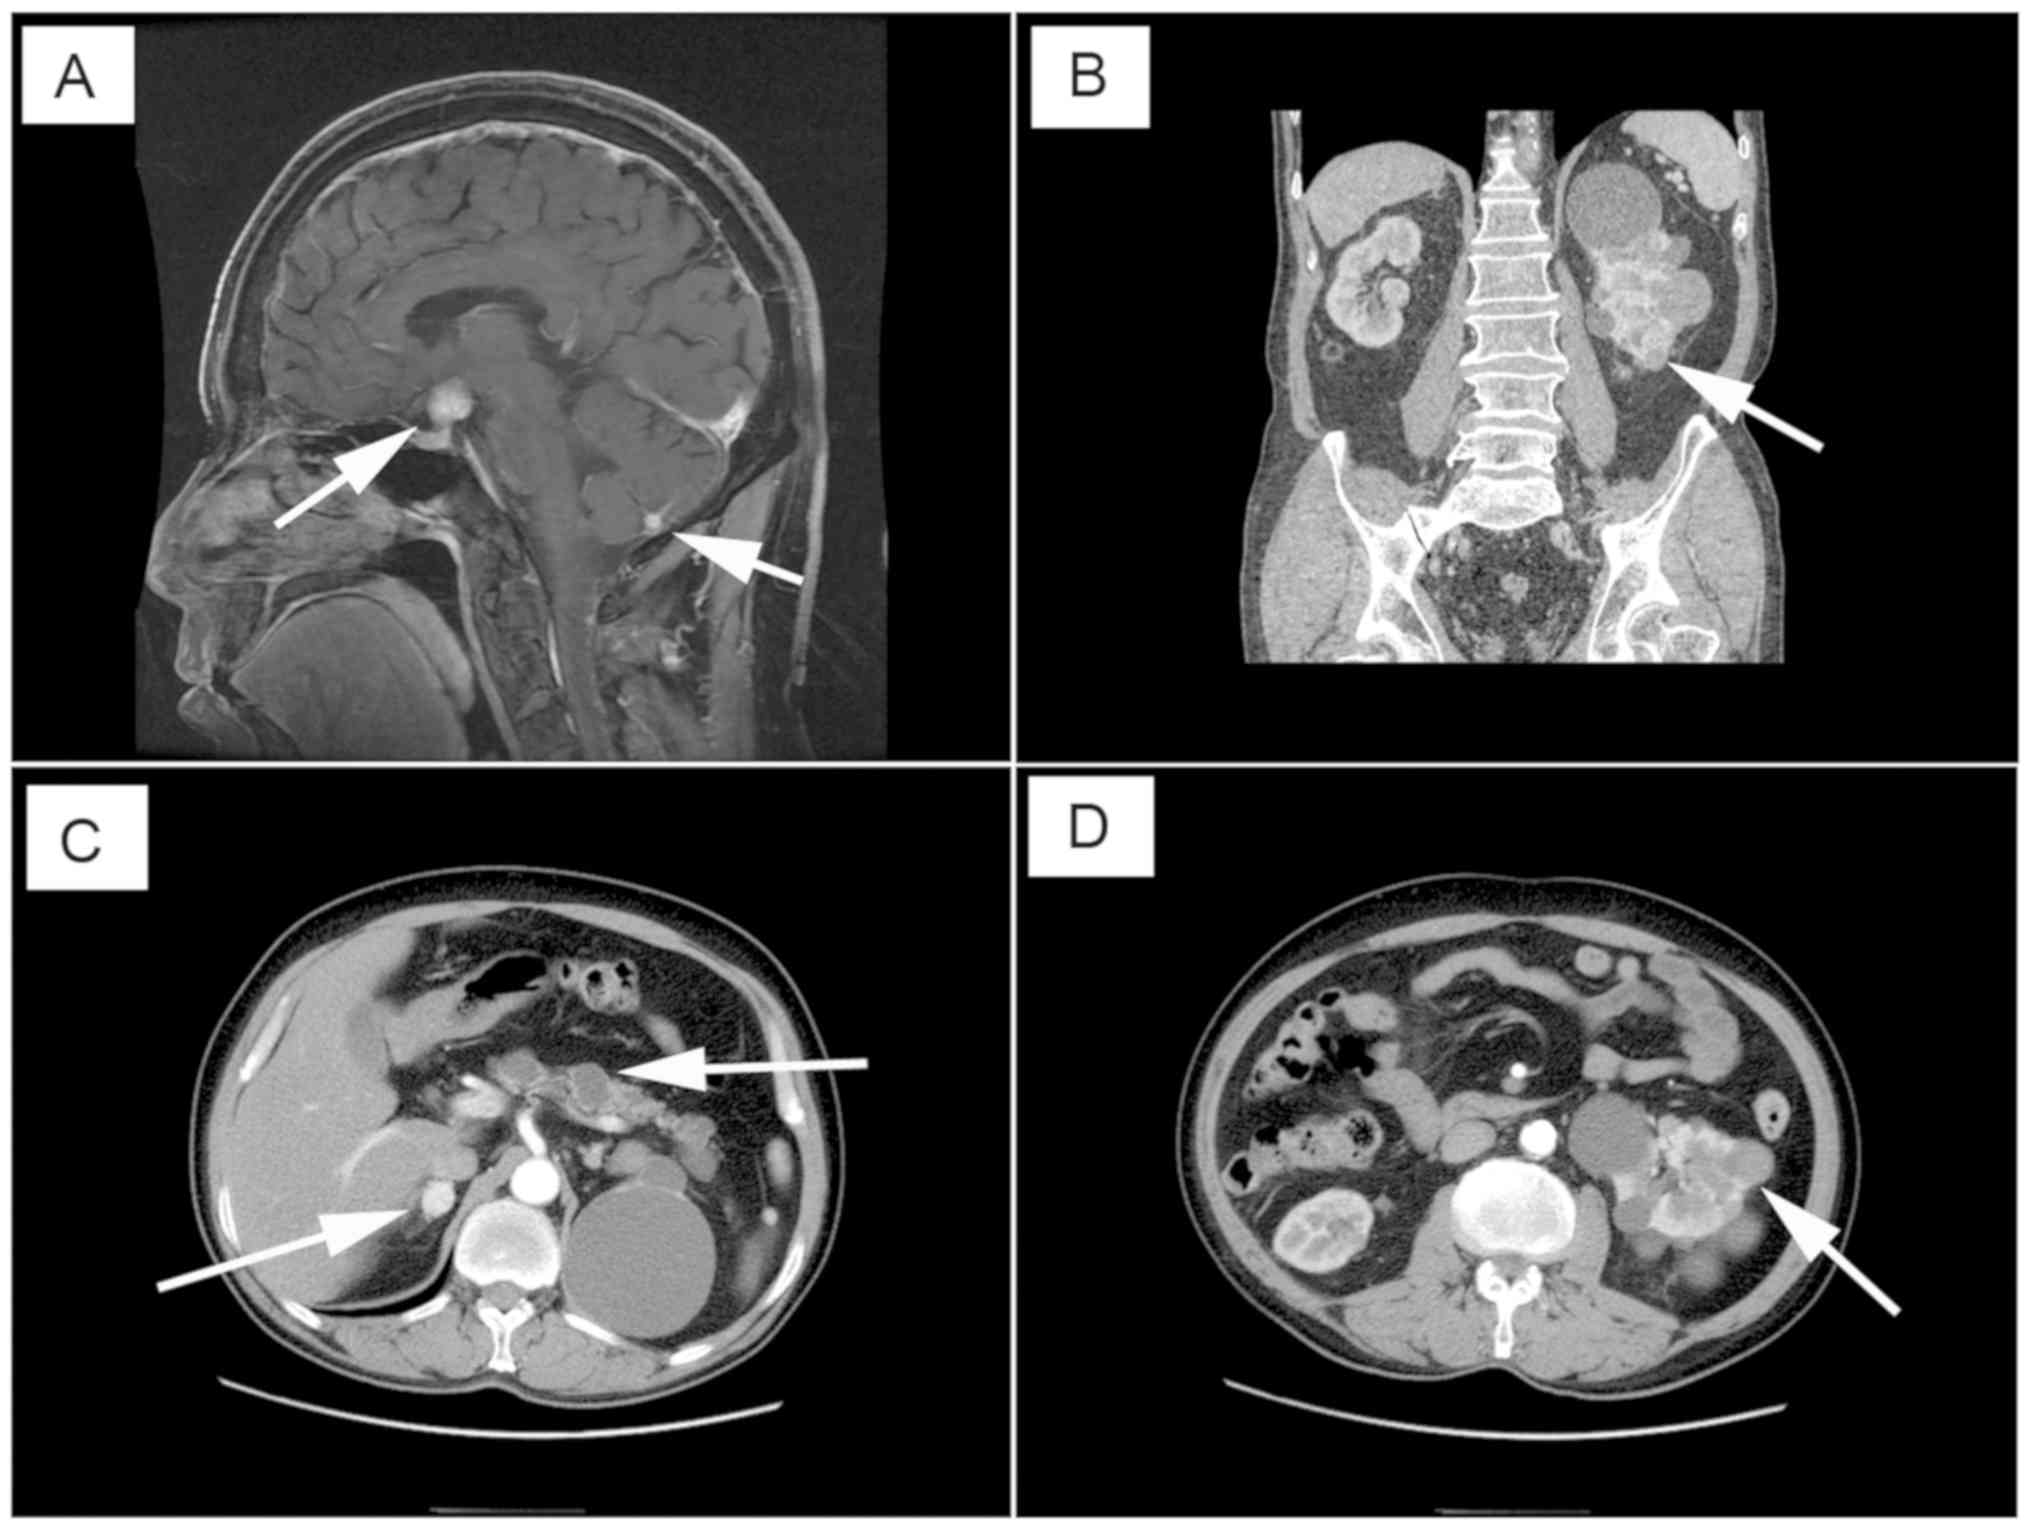

Secondary effects from VHL manifestations are mitigated by routine surveillance and early detection. This article provides an overview of the major clinical histological and radiological findings as well as treatment modalities. The estimated median life expectancy for Chinese patients with VHL disease was 62 years.

Tumors In Von Hippel Lindau Syndrome From Head To Toe Comprehensive State Of The Art Review Radiographics